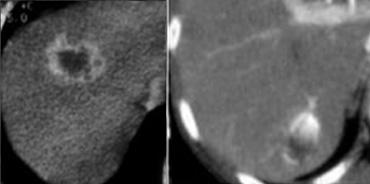

Tổn thương bên trái có các đặc điểm sau:

- Tổn thương giảm tỷ trọng ở thì động mạch và thì tĩnh mạch cửa, với ngấm thuốc ngoại vi.

- Tổn thương tăng tỷ trọng ở thì cân bằng, gợi ý mô xơ đặc.

- Tổn thương gây co rút bao gan.

Hình ảnh một khối thâm nhiễm kèm co rút bao gan và ngấm thuốc muộn kéo dài là đặc trưng điển hình của ung thư đường mật.

Ung thư đường mật thể thâm nhiễm không gây hiệu ứng choán chỗ, vì khi mô đệm trưởng thành, mô xơ sẽ co lại và gây co rút bao gan.

Không có nhiều loại u gây co rút bao gan, vì hầu hết các khối u thường gây phồng lồi bao gan.

Loại u phổ biến nhất gây co rút bao gan ngoài ung thư đường mật là ung thư vú di căn.

Chỉ trên các hình ảnh thì muộn, 8-10 phút sau tiêm thuốc cản quang, mới thấy được tổn thương tương đối tăng tỷ trọng. Đây chính là thành phần xơ của khối u.